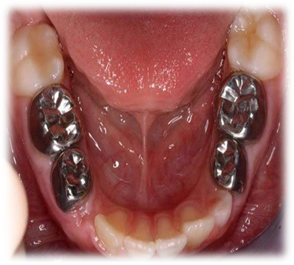

Ø Prevention provide by dentist/what can we do?

Ø Pit and fissure sealant

Ø Provide nearly by 80% protection ,reduce risk of decay in molar

Ø How it works?

Ø By filling cervices and tiny indentation that naturally occurs in teeth and eliminate place for bacteria to breed.